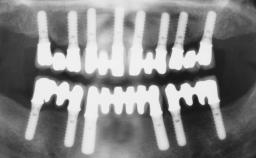

# of Teeth 3

# of Implants 3

Type of Implants One-Piece|Reduced-Diameter

Bone Augmentation Horizontal|Staged|Vertical

Augmentation Materials Autogenous chips|Autogenous block(s)